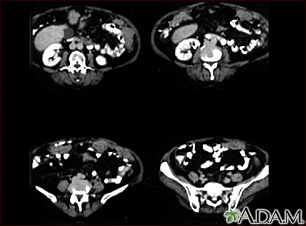

Peritoneal and ovarian cancer, CT scanBackPeritoneal and ovarian cancer, CT scanA CT scan series of the lower abdomen showing ovarian cancer that has metastasized (spread) to the peritoneum. E-mail FormEmail ResultsName:Email address:Recipients Name:Recipients address:Message: